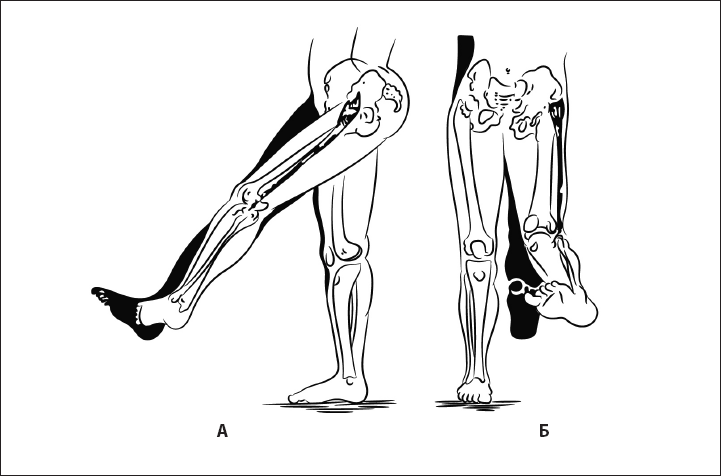

Рис. 25. Шаговый рефлекс, или автоматическая походка. А – норма, Б – отсутствие рефлекса.

Рис. 26. При правильном формировании паттерна шага туловище разворачивается навстречу ноге, согнутой в тазобедренном суставе (работа косых мышц живота). А – вид сбоку, Б – вид сзади.